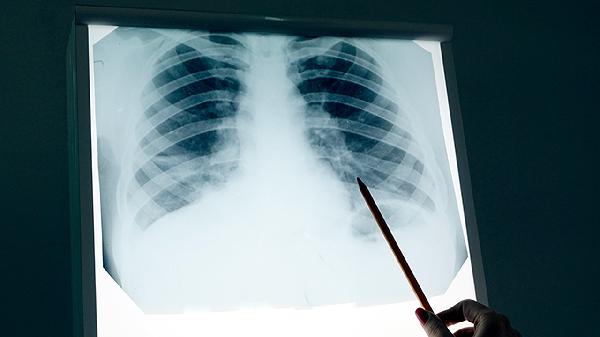

肺鳞癌最好的治疗方案是什么

肺鳞癌的治疗方案需根据病情分期、患者身体状况等因素综合制定,主要手段包括手术切除、放射治疗、化学治疗、靶向治疗及免疫治疗等。早期以手术为主,中晚期需联合放化疗或靶向治疗,免疫治疗适用于特定人群。